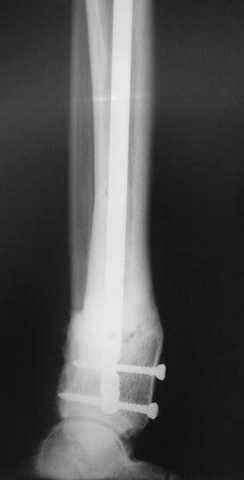

7, 8, 9, 10, 11 - через 8 мес после травмы перелом сросся.

Пациент ходит без дополнительной опоры, не хромает (видеоролик выложил сюда